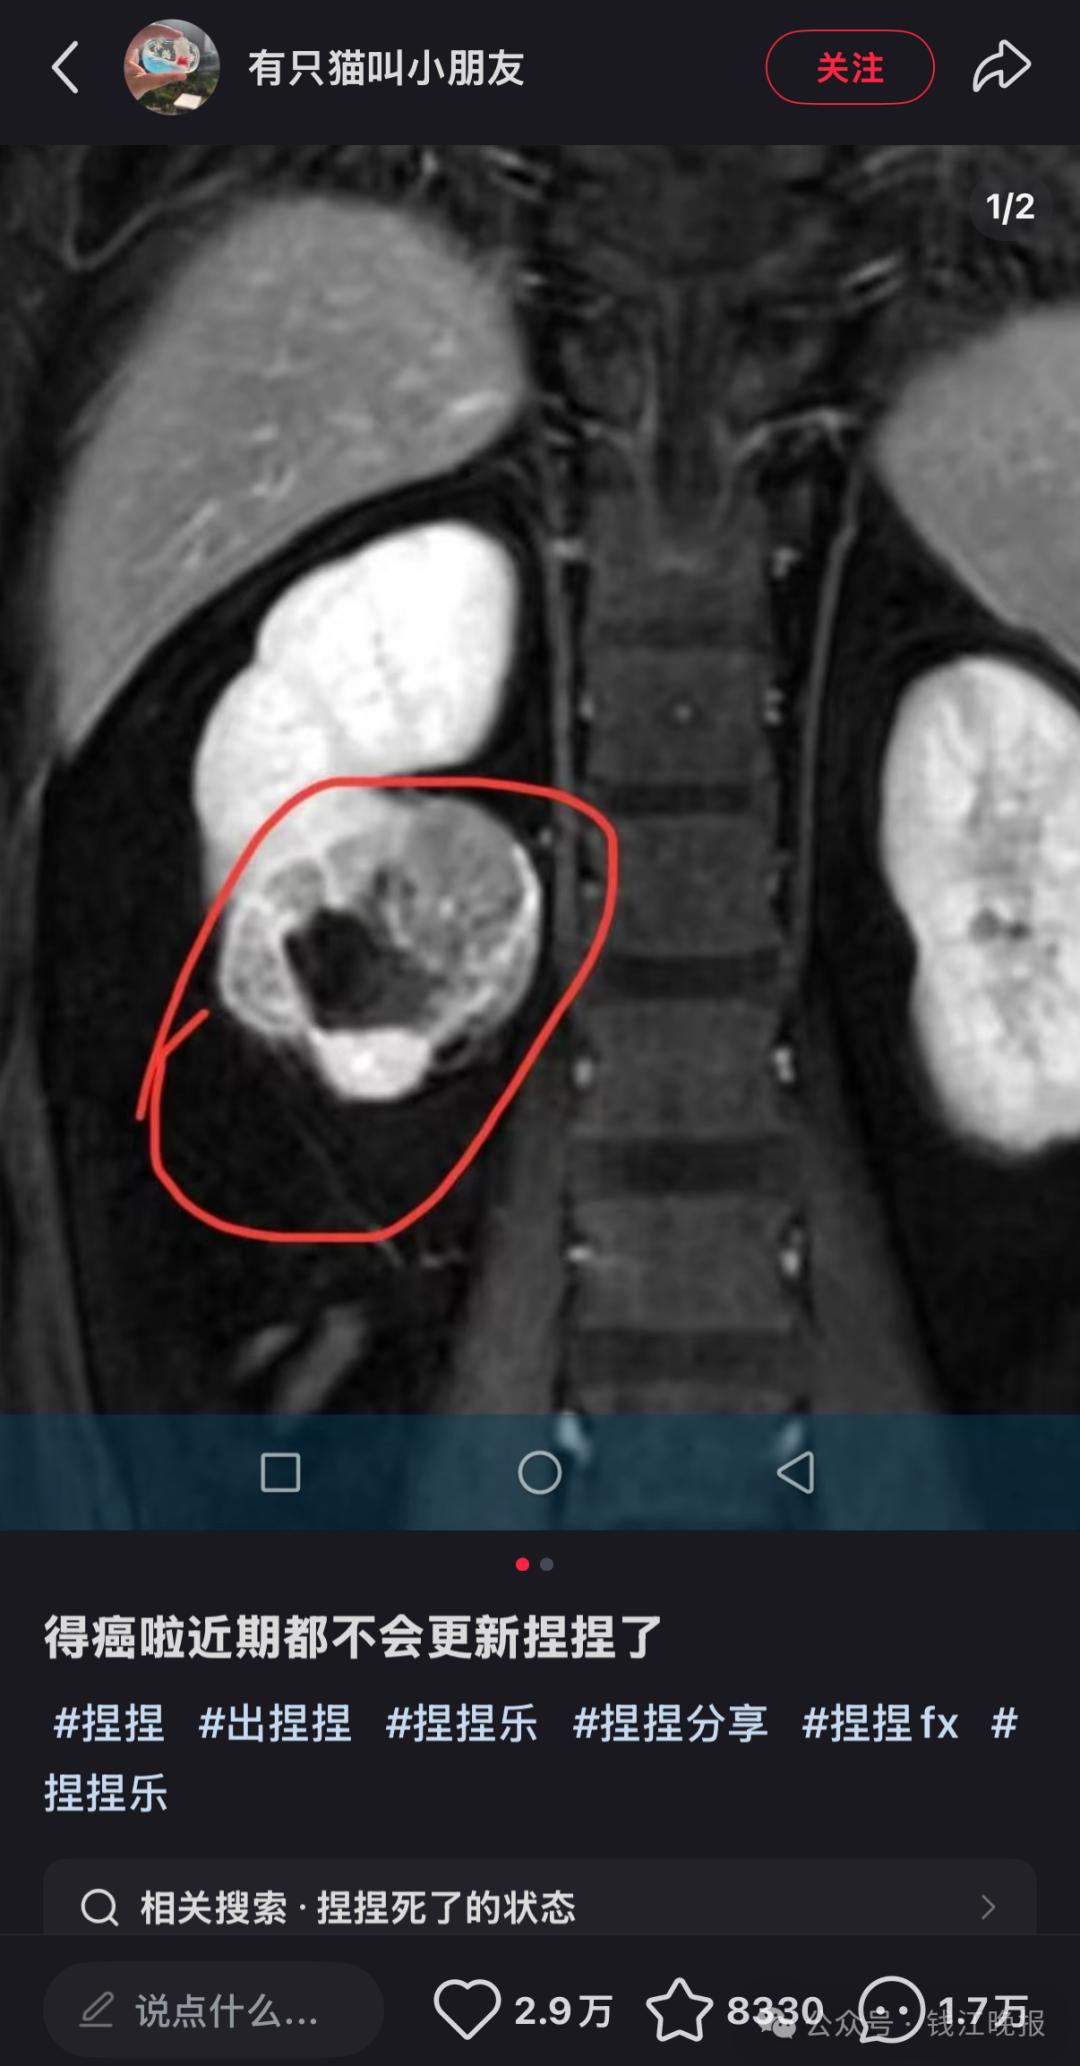

近日,解压玩具博主“有只猫叫小朋友”在社交平台宣布罹患癌症并暂停更新视频。虽然未透露其患病原因,但有网友猜测,是否与其常揉捏“捏捏”玩具有关。由此,也引发了公众对“捏捏”玩具安全性的担忧。

解压玩具博主“有只猫叫小朋友”在社交平台宣布罹患癌症。其“小红书”账号截图